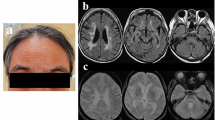

Fc-NTF co-immunoprecipitated with NOTCH3-HA (a). A version of Fc-NTF with all cysteines mutated to serine (Fc-NTF C > S) and the Fc tag alone were unable to pull down NOTCH3-HA. Experiments were performed at least three times using distinct samples with similar results. Unprocessed western blots can be found in Fig. S9. PLA was performed on paraffin-embedded postmortem CADASIL and control brains using an antibody specific for NTF (UMI-F11) and a second antibody recognizing a different epitope of NOTCH3 (1E4; Sigma Aldrich30). Positive PLA signal was identified in 4/4 CADASIL brains and 0/3 age-matched control brains. A representative leptomeningeal vessel from a CADASIL brain is displayed in (b) at ×400 and a representative leptomeningeal vessel from a control is displayed in (c) at ×400. A representative penetrating white matter vessel from a CADASIL brain is displayed in (d) at ×400 magnification and in (f) at ×1000 magnification, and a representative penetrating white matter vessel from a control vessel is displayed in (e) at ×400 magnification and in (g) at ×1000 magnification. Representative vessels from a CADASIL brain stained with UMI-F and 1E4 by immunohistochemistry are shown at ×400 in (h) and (i), respectively.

Second, we tested whether NTF-NOTCH3 interaction could occur in vivo. To do so, we used proximity ligation assay (PLA) with an antibody specific for NTF (UMI-F, which has been shown to be specific for the epitope revealed by cleavage of NOTCH at Asp4111) and an antibody that recognizes an epitope near the middle of the NOTCH3 ectodomain (1E4, EMD Millipore). Positive PLA signal is observed when the two proteins of interest are within 40 nm apart, supporting protein-protein interaction. We found positive PLA signal in 4/4 CADASIL brains (Fig. 3b, d, f) and 0/3 age-matched control brains (Fig. 3c, e, g). PLA signal localization is consistent with medial protein staining and overlaps with regions stained with UMI-F (Fig. 3h) and 1E4 (Fig. 3i).